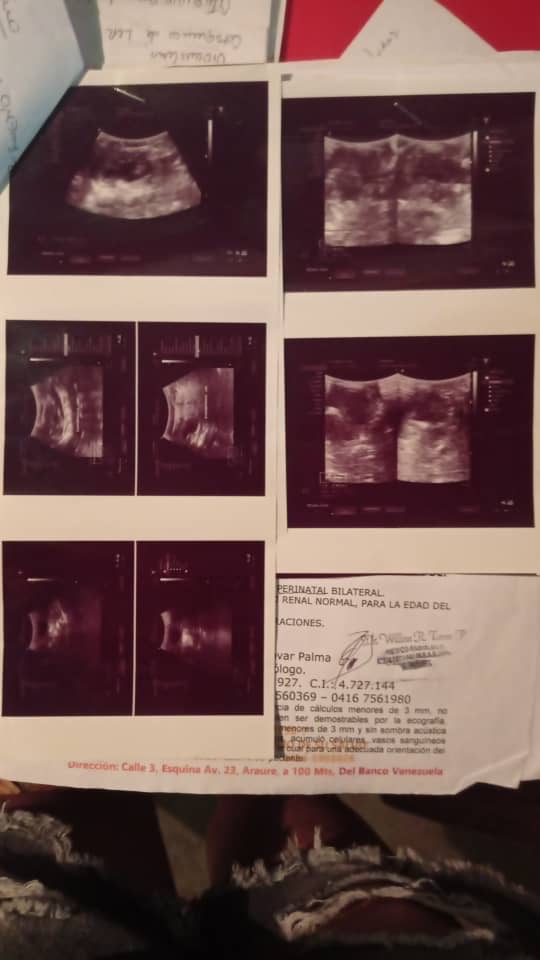

Seguimos en esta lucha y en esta causa hasta lograrlo, poco a poco hemos sumando para que se haga posible todo, gracias a cada personita quea sumado su gran esfuerzo y granito de arena para ir recaudando y poder completar para ser operado, Dios está obrando muy bien en mi vida, así que sigo en pro de ayuda y ahí explico el costo de mi operación, ayúdame compartiendo y difundiendo, ya quiero ser un niño completamente feliz y sano